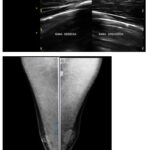

A continuación, la Figura 1 ejemplifica un caso de ginecomastia nodular bilateral, categoría que representa el 34,3% de los patrones ecográficos según la Tabla 1. La ecografía muestra proliferación fibroglandular retroareolar sin vascularización Doppler, concordante con la alta frecuencia de formas bilaterales (68,6%) registradas en el estudio. La mamografía corrobora estos hallazgos al visualizar tejido glandular ectópico bilateral, reforzando la utilidad de la correlación multimodal en el diagnóstico.

Por otro lado, en la Figura 2 se observa un predominio izquierdo en la proliferación fibroglandular, patrón que coincide con el 22,9% de asimetrías izquierdas reportadas en la Tabla 1. La mamografía complementaria evidencia desarrollo glandular retroareolar con claro predominio izquierdo, ilustrando cómo los casos unilaterales (14,3% para izquierda) pueden presentar características morfológicas distintivas, donde tal relación imagen-tabla valida la importancia de evaluar la lateralidad en la planificación terapéutica.

La Figura 3 muestra un caso paradigmático de los hallazgos descritos en la Tabla 2, particularmente similar al caso 7, que presenta ginecomastia bilateral con predominio izquierdo. La imagen ecográfica evidencia con claridad la proliferación fibroglandular con asimetría izquierda, característica que coincide con el 22,9% de casos con predominio unilateral dentro de las formas bilaterales registradas en la serie. Este hallazgo visual corrobora los patrones morfológicos descritos en la tabla, donde las variantes asimétricas representan una proporción significativa de los casos bilaterales.